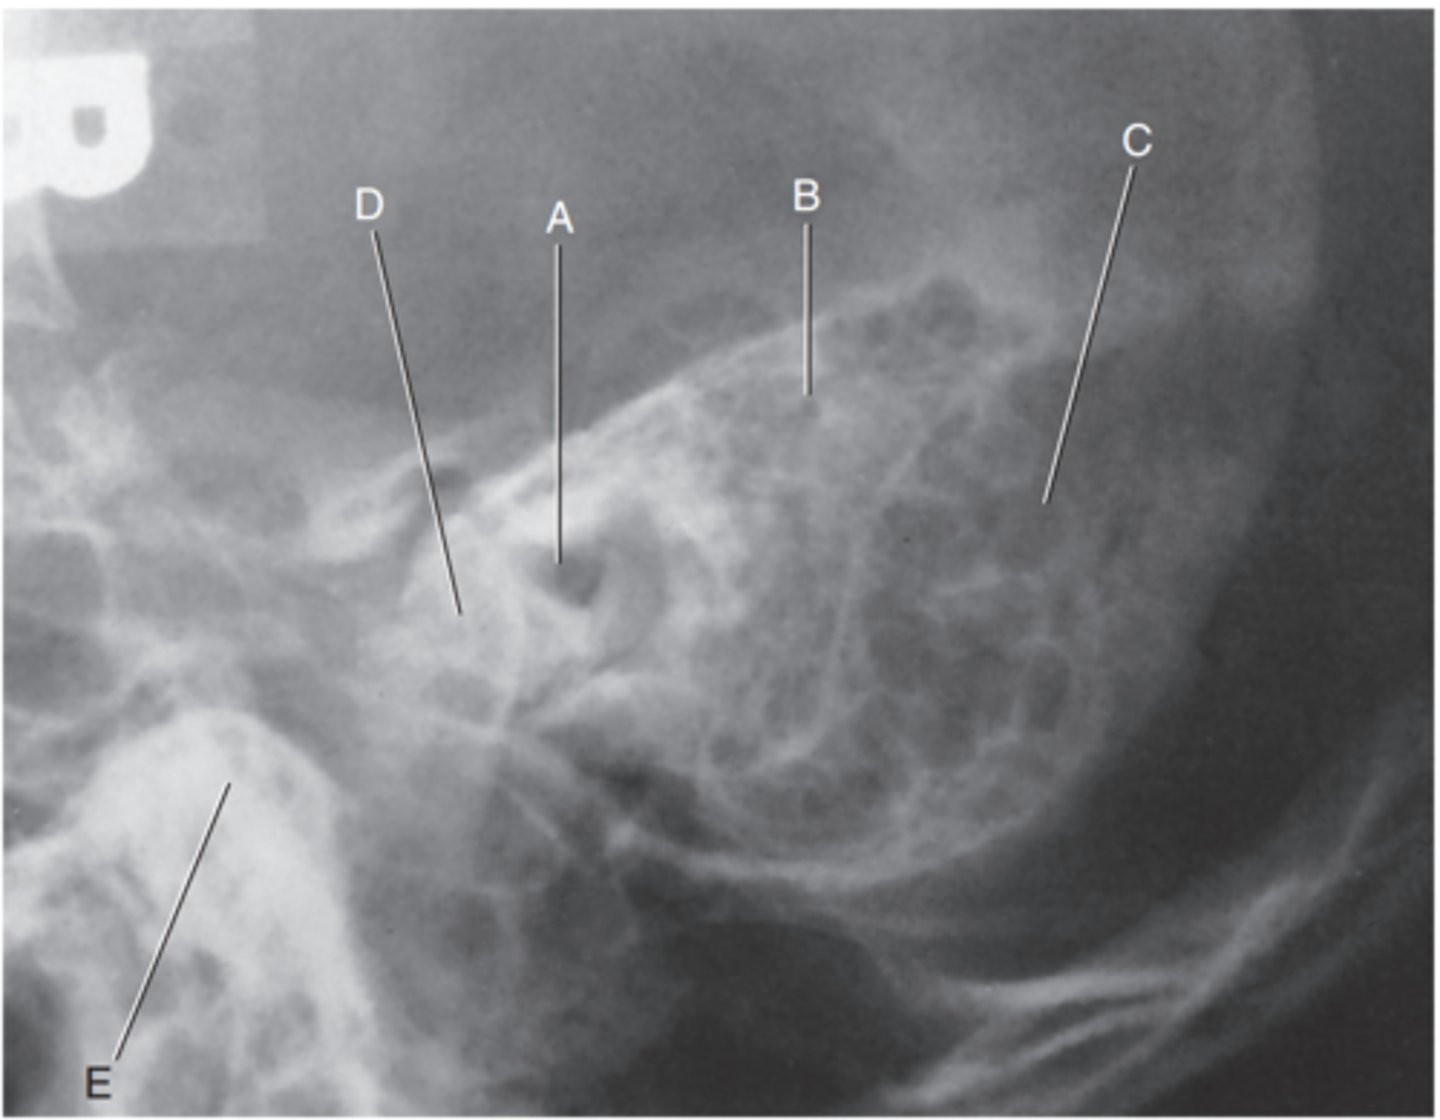

Petrous ridge

Label A

Bony (osseous) labyrinth (semicircular canals)

Label B

EAM

Label C

Region of internal acoustic canal

Label D